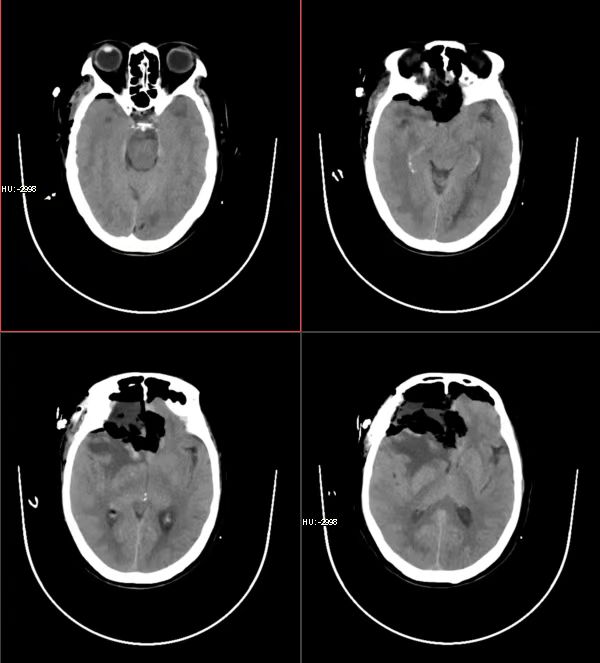

术后影像结果

手术后的危险期也是一道难过的关卡,在此期间,神经外科ICU的医护人员也是给予了精准的治疗与精心的护理。因老人年龄较高,术后病情有一定的波动,每当患者家属因此而产生焦虑时,梁强医师总是耐心的安抚他们的情绪,鼓励家属树立信心,不要放弃治疗。在大家的共同努力下,患者身体状况越来越好,经过14天的治疗,成功渡过了危险期。

康复期间,患者仍就诊于神经外科一病区,潘亚文教授及梁强医师每天查看患者病情,详细讲解需要注意的各种事项,更鼓励患者和家属要有战胜疾病的信心。护士长张兰芳及护理人员不仅给予了他们精心的护理,更为患者带来了贴心的关爱。目前,患者已可以下地短暂行走,83岁的老人获得了重生。